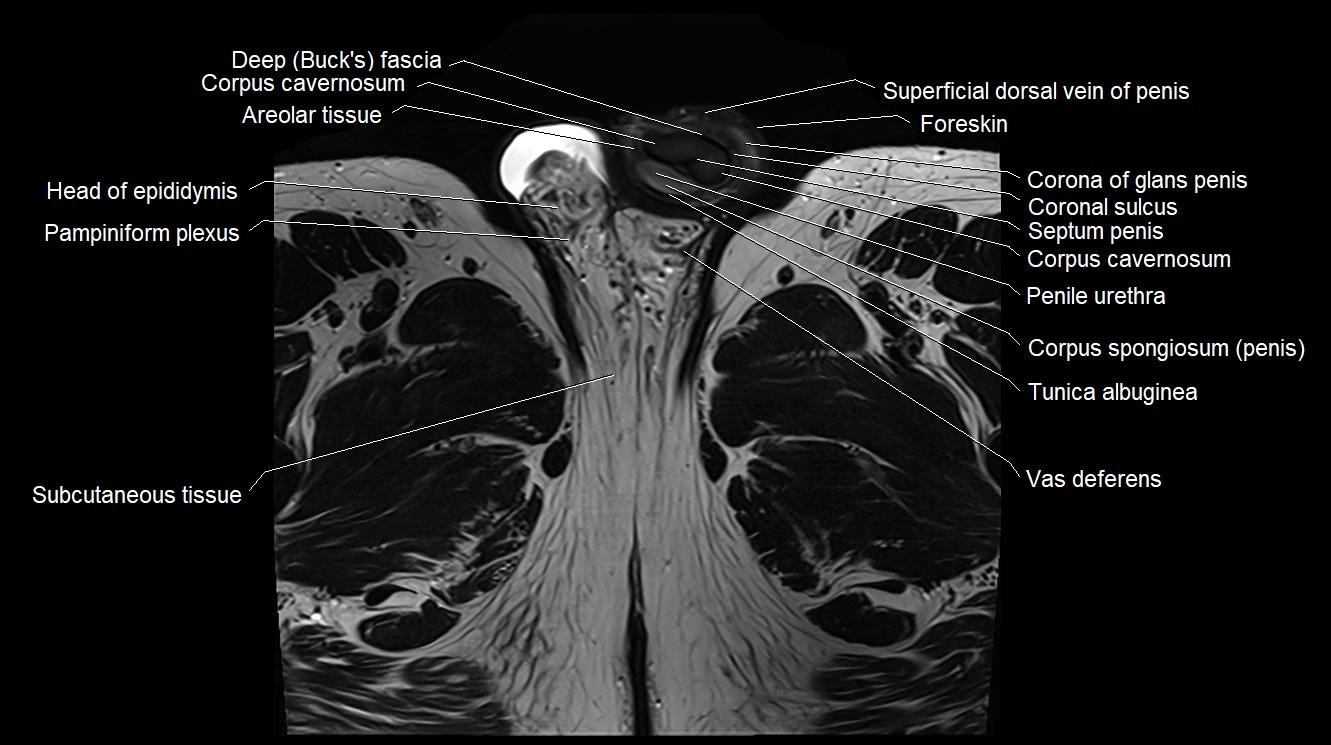

- Areolar tissue of penis

- Buck's fascia (Deep fascia of penis)

- Corona of glans penis

- Coronal sulcus

- Corpus cavernosum

- Corpus spongiosum

- Foreskin

- Head of epididymis

- Pampiniform plexus

- Penile urethra

- Septum of the penis (Penile septum)

- Superficial dorsal vein of penis

- Tunica albuginea (penis)

- Vas deferens